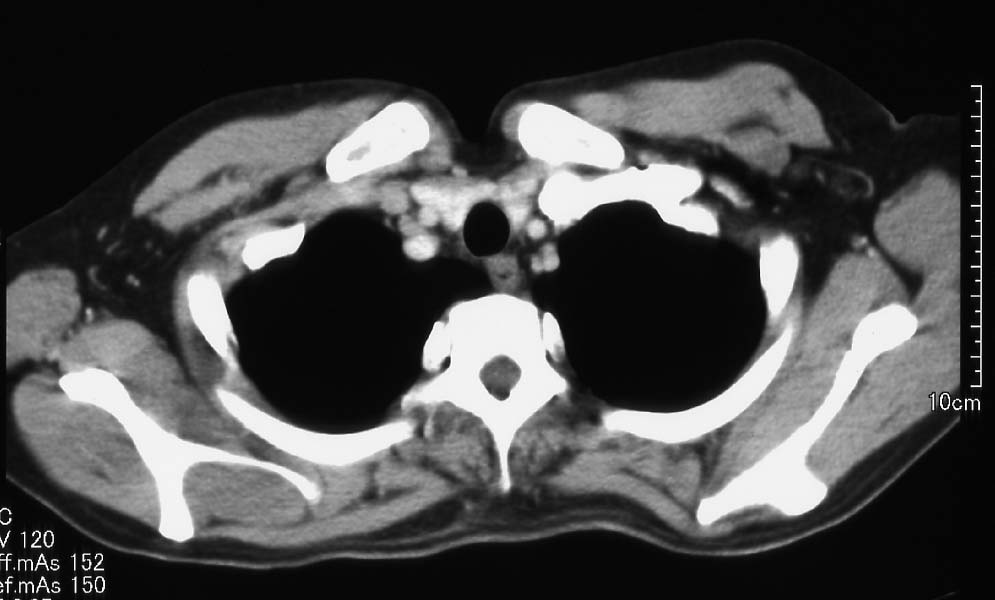

Axillary metastatic lymphnodes showing adenocarcinoma, probbably from breast cancer

- 病理診断:Metastatic carcinoma in the lymph node(原発として乳癌を最も疑う)

- 抗amphiphysin抗体陽性及び病理診断の結果から、原発巣として左乳癌を疑い、左乳房の検査(超音波、マンモグラフィ、MR)を行ったが、FDG-PET同様検出することができなかった。